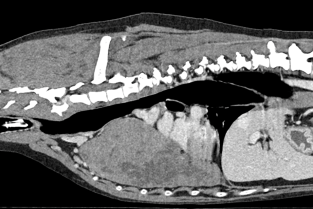

Les journées annuelles du Groupe d'étude en Oncologie (GEO) se consacreront à un focus sur les tumeurs cachées (intrathoraciques, costales, médiastiales, pulmonaires…) et sur des tumeurs de localisation rare (tumeurs rectales, ou périanales, comprenant les carcinomes des sacs anaux) : comment les mettre en évidence, en diagnostiquer la nature, les prendre en charge, de la chirurgie à la thérapie adjuvante ou palliative. Enfin, comment évaluer la qualité de vie des animaux cancéreux et améliorer la prise en charge aussi sur ce plan-là.

- Reconnaître les manifestations cliniques des masses intrathoraciques et les localiser (pleurales, médiastinales, pulmonaires, costales).

- Utiliser l’imagerie (échographie, scanner) et savoir quand recourir à une ponction ou une biopsie intrathoraciques.